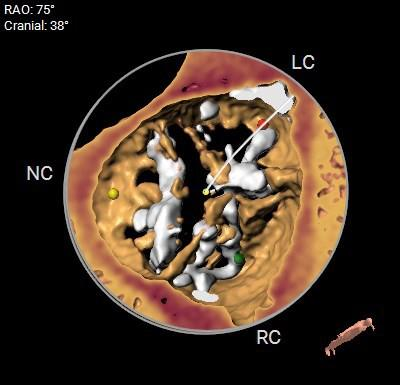

术前CT评估

1.CT数据显示该患者Type 1型二叶式主动脉瓣,左右钙化融合,瓣叶重度钙化并增厚,钙化分布较均匀,主要分布在无冠侧瓣叶边缘及左右交界。

2.主动脉瓣瓣环周长95.7mm,平均周长径30.5mm。

主动脉根部及外周入路预览

主动脉根部测量

冠脉阻挡风险及左室大小评估

瓣上测量

钙化分布

弓角弓距及瓣环角度